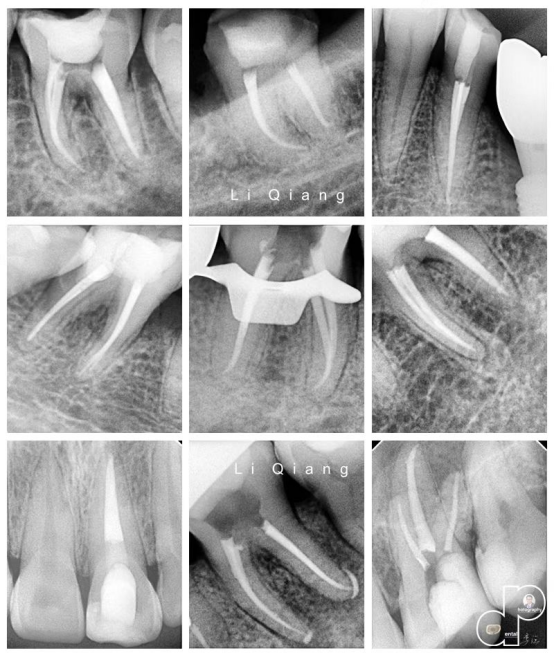

橡皮障隔离系统的组成,及在根管治疗中的使用演示。学员实操练习使用橡皮障 龈壁提升邻面洞型的恢复,开髓冠方直线通路的建立,根管口的查找离体牙演示及学员实操练习

手动锉的探查与疏通 根管长度与根管预备长度的确定 根管预备的宽度确定 根管预备的逐步后退法 根管预备的冠向下法 弯曲根管的预备方法 根管化学预备的常用药物及浓度 化学预备的器械与药物使用步骤 实操:在透明模块和离体牙上实操镍钛锉根管预备

常用根管封药及选择 根管封药与难治性根尖周炎的控制 合适主尖的确定 常用根管糊剂的特性及选择 单尖法根管充填步骤方法 热牙胶垂直加压技术 热牙胶连续波技术 实操:老师在模型上示教单尖法及热牙胶充分步骤方法,学员同步实操。